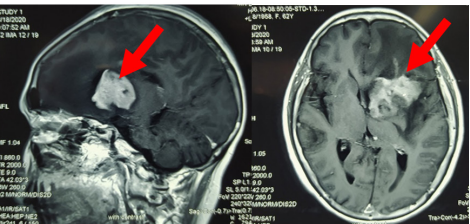

Tại một bệnh viện lớn của TP.HCM, kết quả chụp cộng hưởng từ (MRI) sọ não phát hiện bà có tổn thương nhu mô não vùng trán trái, kích thước 43x33x35mm, phù nề não xung quanh, đè ép não thất bên bên trái.

Người bệnh sau đó được chuyển đến Bệnh viện Quân y 175 tiếp tục điều trị. Các bác sĩ tiến hành hội chẩn giữa khoa ngoại thần kinh, hóa trị, xạ trị, chẩn đoán hình ảnh, giải phẫu bệnh, thống nhất chẩn đoán xác định bà bị u lympho não nguyên phát.